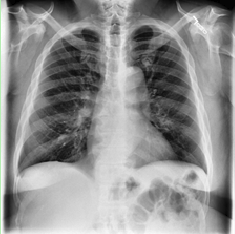

The dataset download from Kaggle[18] which has training image and their masks. The masks are encoded in RLE(Run Lenght Encoding) and we have used the same algorithm to decode the mask image. We kept some of the training images for testing and validating the model after training. Dataset has good amount of the images. In the dataset we have 12047 images and same number of masks. Images are in shape 256 x 256. If an image does not have Pneumothorax then it’s mask is all black. The all black mask image teaches the model which X-ray images does not have Pneumothorax. We will be keeping 20% of the images for testing and validating the model.

Refer to caption

Figure 4: Chest X-ray Images